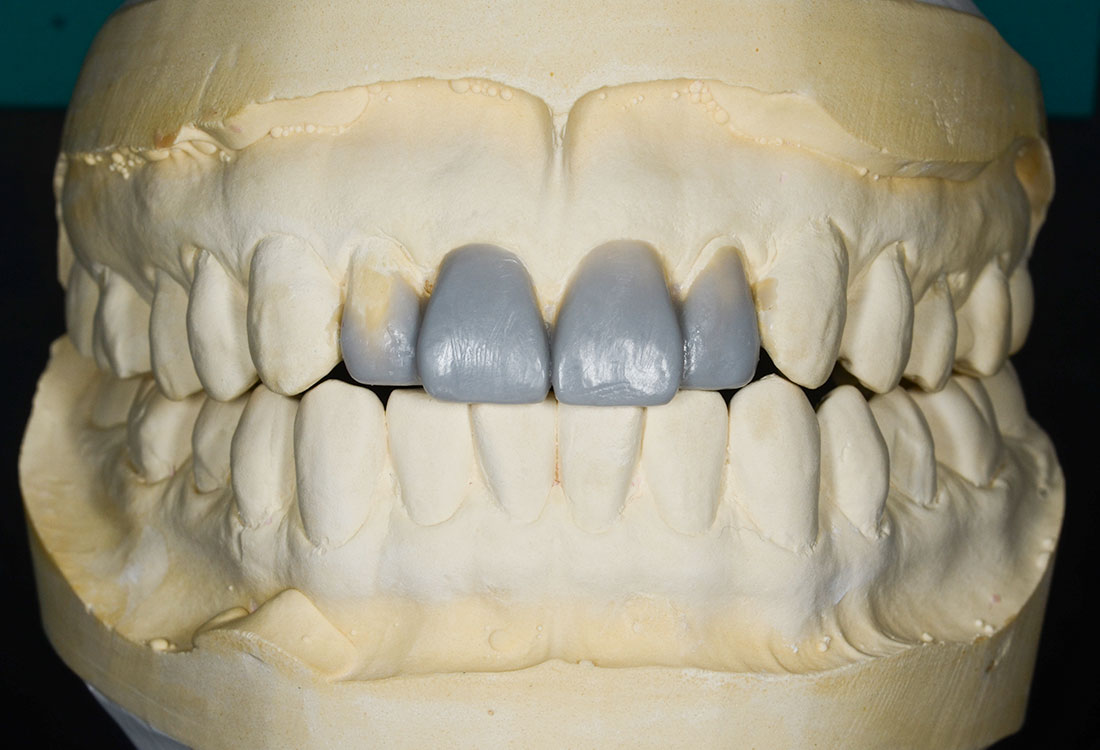

治療内容

模型を作成して最終的な形を模索します。

土台になる歯の形を整えて最終的な形の模型を作ります。